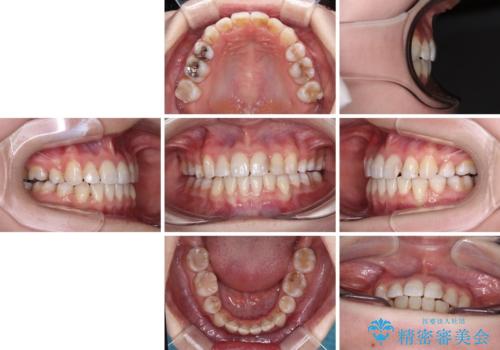

八重歯のためずれていた上下の正中をほぼ一致する位置に整えることができました。

重なって汚れの溜まりやすかった部分も改善され、大変満足していただけました。